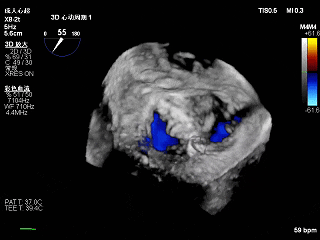

3D-ZOOM 彩色多普勒显示反流主要来源于2区

3D下大鞘的穿刺位置大概在3点钟方向

夹子关小后3D观察组织桥

夹子释放后3D下观察组织桥稳定,反流降至trace